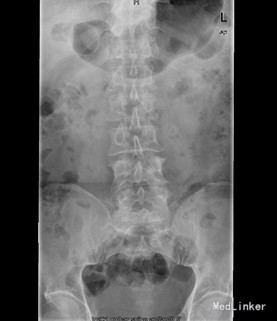

患者男,60岁,因“反复双下肢疼痛麻木4+年,加重伴腰痛4+月”入院。 入院前4+年患者无明显诱因出现右下肢麻木疼痛,呈持续性放射痛,无腰痛及下肢活动受限,4+月前患者无明显诱因出现双下肢反复交替麻木疼痛,呈放射性疼痛,双侧大腿后方小腿外侧及足背感觉麻木,以右侧较重,同时出现腰骶部疼痛,疼痛明显时患者出现跛行步态伴腰部活动受限, 今进一步治疗遂入我院。

查体:腰4、5棘突轻度叩压痛,双侧大腿后外侧小腿外侧及足背感觉功能减退,以右侧明显。 辅查:CT示腰4椎体骨质破坏并增生、硬化改变,以骨质破坏为主,左侧椎旁软组织肿块形成,结核?肿瘤待排。腰4、5腰5骶1椎间盘突出。腰椎退行性变。MRI示腰4椎体骨质破坏,性质?腰4、5腰5骶1椎间盘突出,腰椎退行性变,双侧髂骨信号不均匀,性质?

初步诊断:腰4椎体骨质破坏:结核?肿瘤? 诊疗计划:经前路腰4椎体部分切除,椎管减压,取自体髂骨植骨融合,Antares内固定术